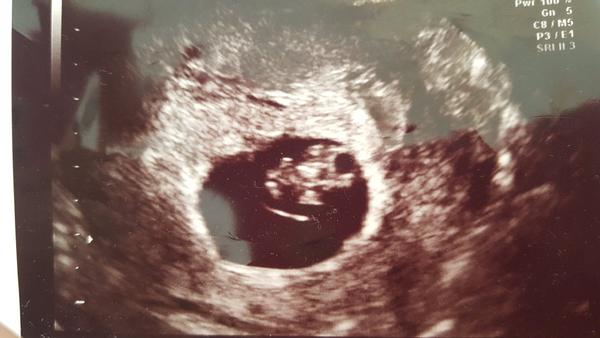

@korytkaja mame sa dobre a ano mala som v piatok sono a vsetko je v poriadku.Teraz sme 8tt+2 tak sa vytesujeme 🙂 A ty sa mas ako?

fotecku mi az teraz ukazalo ❤ krasny drobcek.. Ja este nemam lebo mala pokazenu tu vec. Ale 8. sa dockam fotecky aj ja 🙂